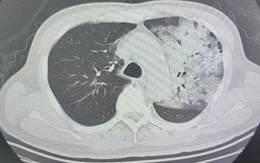

Người đàn ông sốt 40 độ C, phổi gần như 'trắng xóa", chỉ vài ngày đã suy đa tạng: Thủ phạm liên quan đến thói quen nhiều gia đình vẫn mắc

Một chiếc điều hòa lâu ngày không được vệ sinh có thể tiềm ẩn rủi ro sức khỏe nghiêm trọng mà nhiều người không ngờ tới.